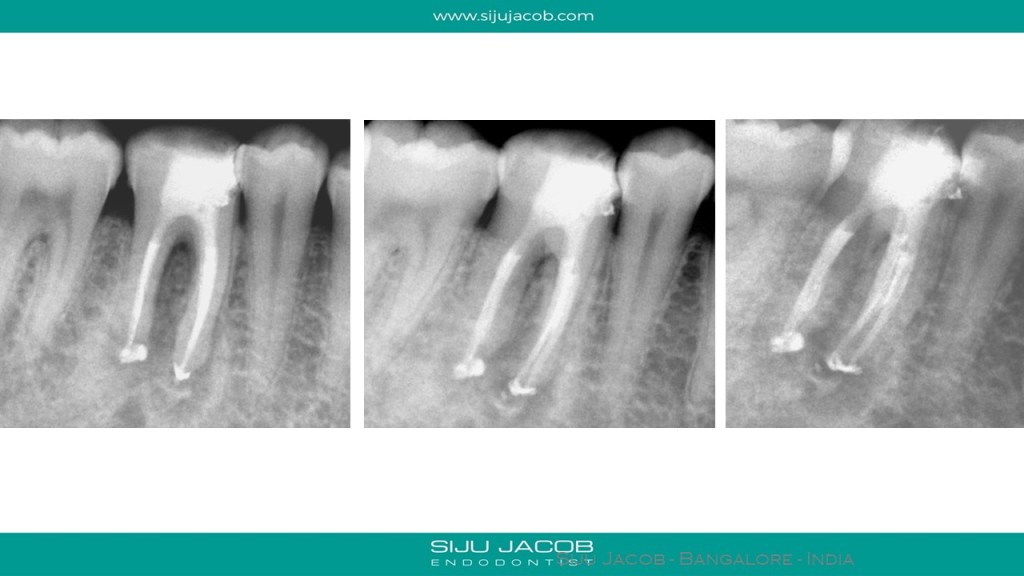

This is a garden variety middle-mesial canal i tretaed in 2009. The crown done by the referral was a bummer. Patient came back a year later with discomfort. The periapical lesion had healed, but the crown had an open margin leading to food impaction. I suggested changing the crown. Liviu Steier requested that I convert this case into a small article for Dental tribune U.K. Attached is the pdf from 2009.